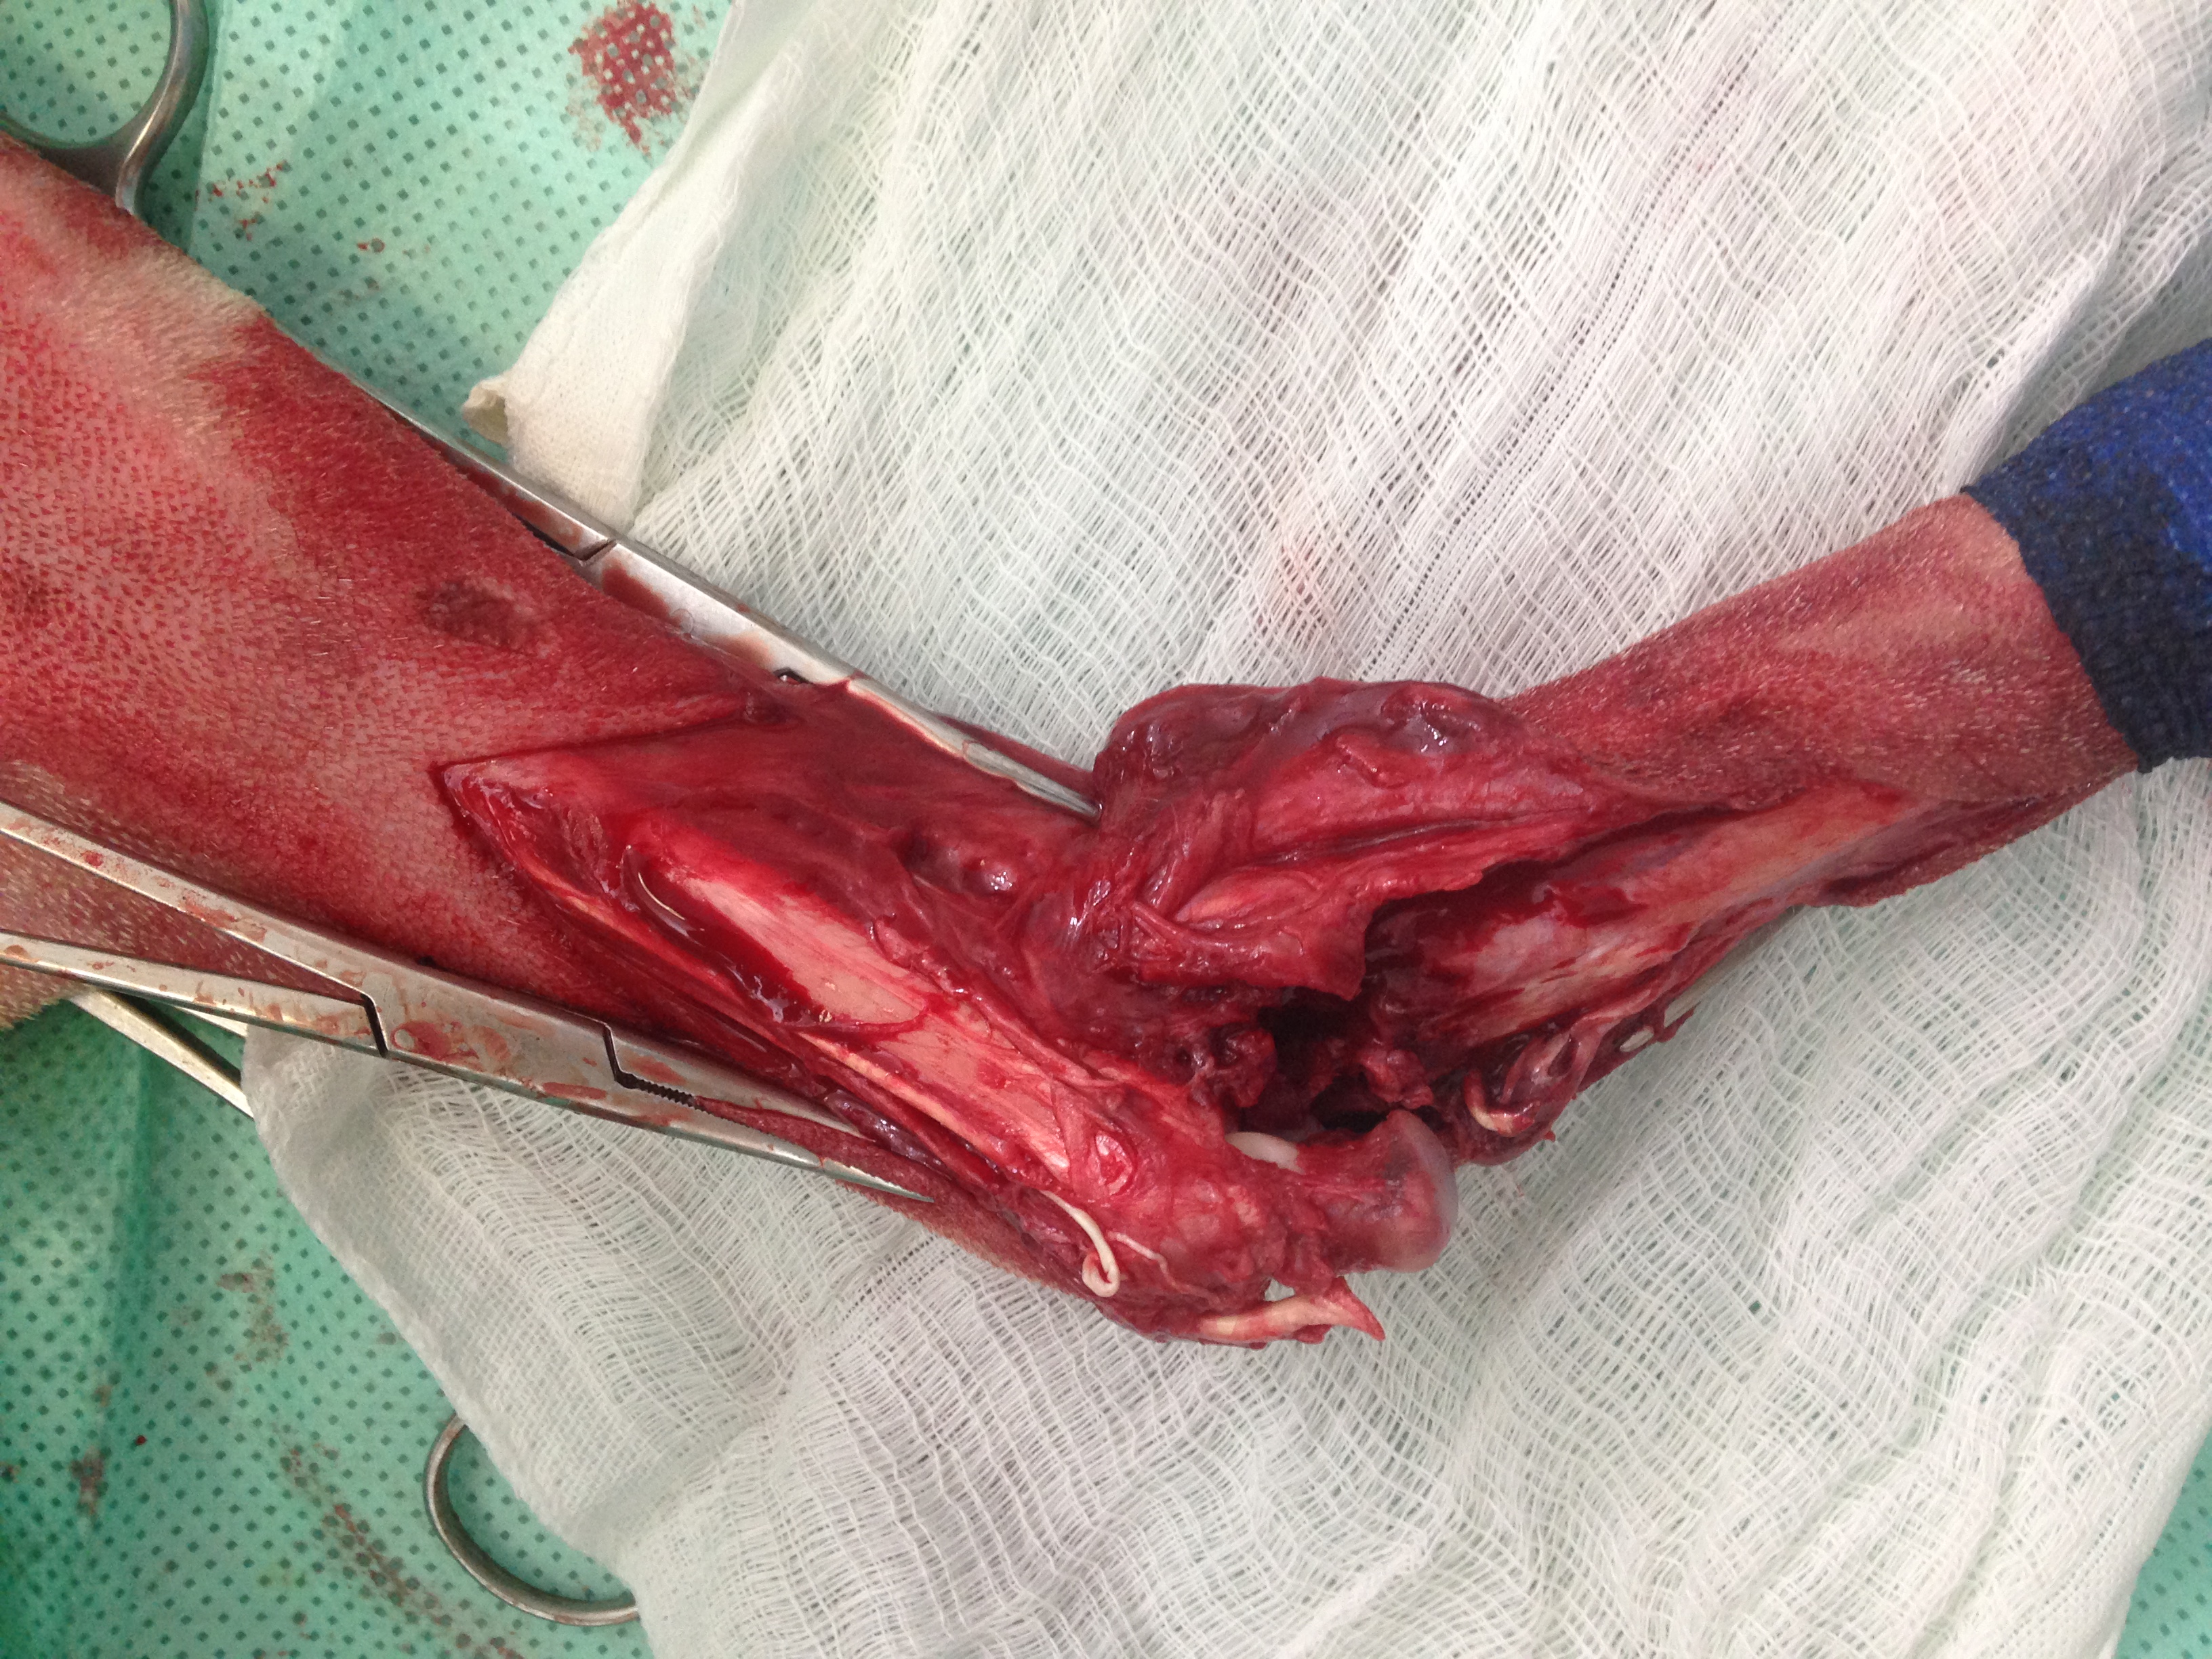

Casos Interessantes > ARTRODESE Tíbio-Tarsica por placa medial

Veja algumas Fotos